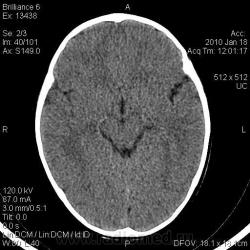

Ребёнок коллеги из нашей больницы, 1 г. 9 мес. С 1,5 месячного возраста отмечали небольшую припухлось в левой теменно-височной области, которая постепенно увеличивалась с ростом ребёнка. Припухлость расценивалась как лимфоузел, однако в связи с длительным характером процесса решили дообследовать. Доктор, выполнявший УЗИ, сообщил, что на лимфоузел это не похоже, и он не видит кости под образованием. Выполнили рентгенографию, затем - КТ.

Полной ясности нет. Мы думаем о: 1. Эозинофильной гранулёме.

2. Дермоидной кисте? Фиброме? Др. мягкотканной опухоли?, которая, постепенно оказывая давление на кость, вызвала атрофию костной ткани.

3. Каком-то врождённом нарушении оссификации кости черепа?

Наиболее вероятен дермоид. Округлый костный дефект с четкими ровными контурами - атрофия от давления. Дефект в наружной пластике больше, чем во внутренней (блюдцеобразный дефект). Плотность образования вероятно жировая. Локализация на границе швов также более характерна для дермоида. Фибромы гораздо плотнее, вряд ли вызовут атрофию от давления, никогда не слышала о таком, доброкачественным опухолям проще расти кнаружи, чем разрушать кость. Часто фибромы достигают значительных размеров и не вызывают атрофию от давления. Интересно образование плотное или мягкое, четко отграниченное, с гладкой поверхностью?

Безболезненность и плотность образования говорит в пользу дермоида. Контуры нечеткие? А как же сравнения с лимфоузлом? Возможно контуры скрадывают мягкие ткани головы, тем более само образование маленькое. Если КТ делали у Вас, попросите измерить плотность. А контуры дефекта действительно гладкие, подчеркнутые? Я не ошибаюсь? Не очень хорошо видно на КТ, слишком мелко.

Контуры гладкие. Плотность от 14 до 27 HU.

Я тоже думаю, что больше данных за дермоид.

Согласен с версией дермоид; в образовании есть участки низкой плотности сопоставимыми с плотностью жира, что является характерным признаком при дермоидах.

Спасибо, коллеги, за помощь. Похоже, это действительно дермоидная киста.